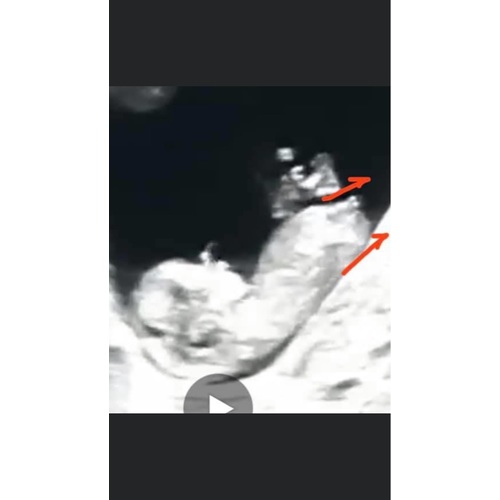

12 weken en 1 dag. Iemand een idee jongen of meisje 🥰

12 weekjes

Ik neig naar jongetje. Had je nog een tweede foto toevallig?